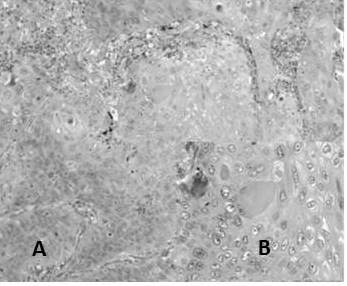

OTROS DIAGNÓSTICOS RECLASIFICADOS

Posteriormente al reclasificar la totalidad de los casos ascendió la cifra de casos catalogados como otras lesiones a 22 casos en los cuales se observaron: 12 casos de carcinoma no clasificable, 8 casos por muestra escasa y 4 casos por necrosis extensa (Figura 18), 7 casos fueron reclasificados como metaplasia escamosa (no tumoral), 2 casos de carcinoma sarcomatoide (Figura 19) y 1 caso inflamatorio (no tumoral) (Cuadro 12)

No obstante las lesiones reclasificadas como otras lesiones presentaron previamente diagnósticos de: 9 casos de carcinoma de células escamosas, 8 casos de adenocarcinoma poco diferenciado, finalmente casos con diagnóstico sugestivo de adenocarcinoma (2 casos) y casos de carcinoma moderadamente diferenciado (2 casos) (Cuadro 11 y 12)